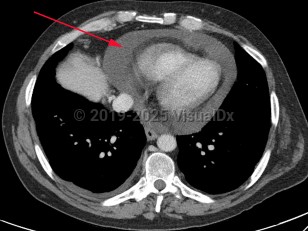

Anasarca, 50-59 year old Female

Pericardial effusionPericardial effusion